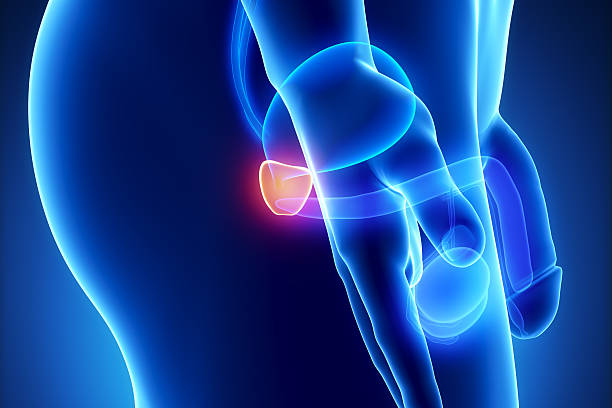

전립선은 남성 생식 기관으로 정자로 들어가는 체액을 생성하는 역할을 합니다. 이러한 전립선액은 남성 생식력에 필수적으로 샘은 방광의 목에 있는 요도를 둘러싸고 있습니다. 방광경부는 요도가 방광과 만나는 곳으로 방광과 요도는 하부 요로의 일부입니다. 전립선은 조직의 바깥층으로 둘러싸인 두 개 이상의 엽 또는 섹션을 가지고 있으며 방광 아래 직장 앞에 위치하며 요도는 방광에서 몸 밖으로 소변을 운반하는 관으로 요도는 음경을 통해 정액을 운반하는데 그 부위에 염증이 생기는 것을 전립선염이라고 합니다. 이러한 증상은 전립선 및 때로는 전립선 주변 부위의 염증과 관련된 지속적인 통증이 생기는 것을 의미하며 이번 시간에는 전립선염으로 생길 수 있는 여러 증상에 대해 정리해보겠습니다.